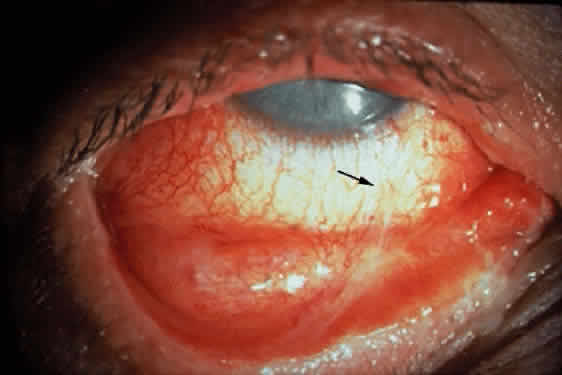

Fibrosis beneath the conjunctival epithelium is the hallmark of CP.9,10 Symblepharons, fibrotic bands that pass between the palpebral and bulbar conjunctiva, involve the inferior fornix first and are best demonstrated early in the disease by drawing the lower eyelid down and having the patient look up (Fig. 3). CP may be associated with a dry eye. Fibrosis beneath the conjunctival epithelium may cause occlusion of the ducts of the lacrimal and accessory lacrimal glands, leading to decreased aqueous tear secretion. The reduced numbers of mucus-producing goblet cells may contribute to an unstable tear film.11 Conjunctival scarring causes lagophthalmos with abnormal blinking and exposure and entropion with trichiasis and distichiasis. All these factors may cause breakdown of the ocular-surface epithelium.

Cicatricial pemphigoid generally runs a chronic course, characterized by progressive shrinkage of the conjunctiva. When the end stage of this disease is reached, the eye lacks tears and has obliterated conjunctival fornices, ankyloblepharon, and a keratinized ocular surface epithelium. Episodes of acute disease activity may interrupt this chronic progressive course and result in rapid shrinkage of the conjunctiva.15 Acute disease activity may be precipitated by surgical procedures, including conjunctival biopsy, lysis of symblepharon, oculoplastic procedures on the eyelids, and cataract extraction. The acute manifestations consist of localized, ulcerated conjunctival mounds (Fig. 4) or diffuse, severe conjunctival hyperemia and edema (Fig. 5). Before concluding that acute inflammatory activity is caused by the disease process, it is necessary to eliminate other confounding factors such as trichiasis, exposure, or bacterial blepharoconjunctivitis.